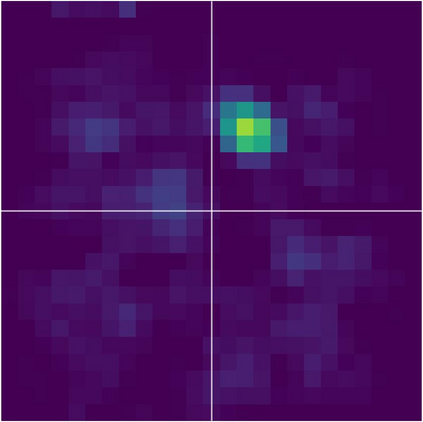

Various imaging modalities allow for time-dependent image reconstructions from measurements where its acquisition also has a time-dependent nature. Magnetic particle imaging (MPI) falls into this class of imaging modalities and it thus also provides a dynamic inverse problem. Without proper consideration of the dynamic behavior, motion artifacts in the reconstruction become an issue. More sophisticated methods need to be developed and applied to the reconstruction of the time-dependent sequences of images. In this context, we investigate the incorporation of motion priors in terms of certain flow-parameter-dependent PDEs in the reconstruction process of time-dependent 3D images in magnetic particle imaging. The present work comprises the method development for a general 3D+time setting for time-dependent linear forward operators, analytical investigation of necessary properties in the MPI forward operator, modeling aspects in dynamic MPI, and extensive numerical experiments on 3D+time imaging including simulated data as well as measurements from a rotation phantom and in-vivo data from a mouse.